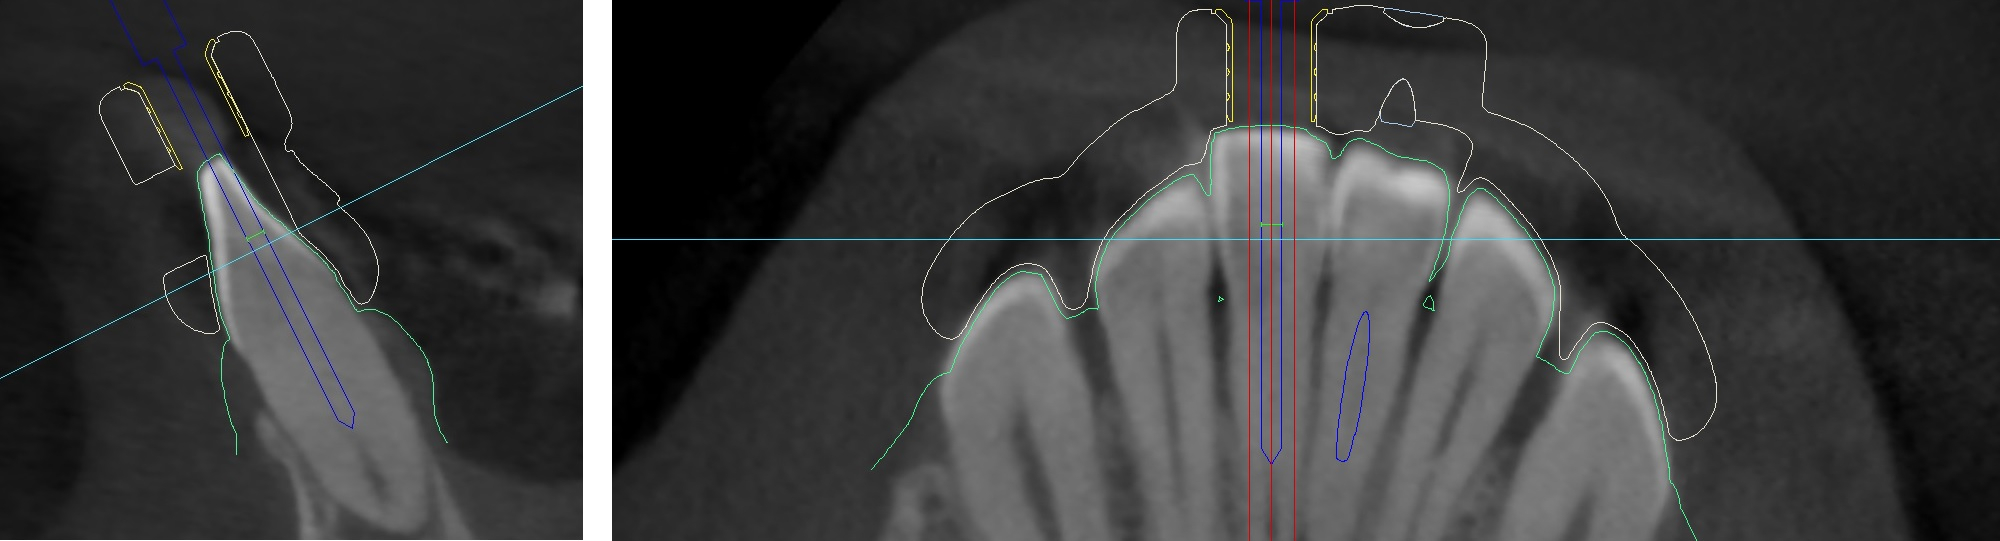

Bohrachse am Computer definieren, Planungssoftware coDiagnostiX™

Auf Basis dreidimensionaler Röntgenverfahren, lassen sich die Strukturen obliterierter Zähne virtuell darstellen.

Hierbei verwenden wir die Planungssoftware coDiagnostiX™, die sich bereits in der Implantatplanung bewährt hat. Üblichweise dienen DICOM

Daten als Basis für die softwarebasierte Planung. Der Zugang zur Kavität kann in der Software präzise geplant und die

Bohrachse entsprechend ausgerichtet werden. Sinnvoll ist hierbei auch die Darstellung der Bohrergeometrie.